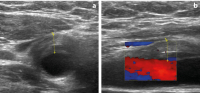

TIPIC-Syndrom – ein seltenes Krankheitsbild mit perivaskulärer Inflammation der A. carotis: Literaturreview // TIPIC syndrome – a rare disease with perivascular inflammation of the carotid artery – literature review

Zeitschrift für Gefäßmedizin 2025; 22 (1-2): 5-13 Volltext (PDF) Summary Praxisrelevanz Abbildungen